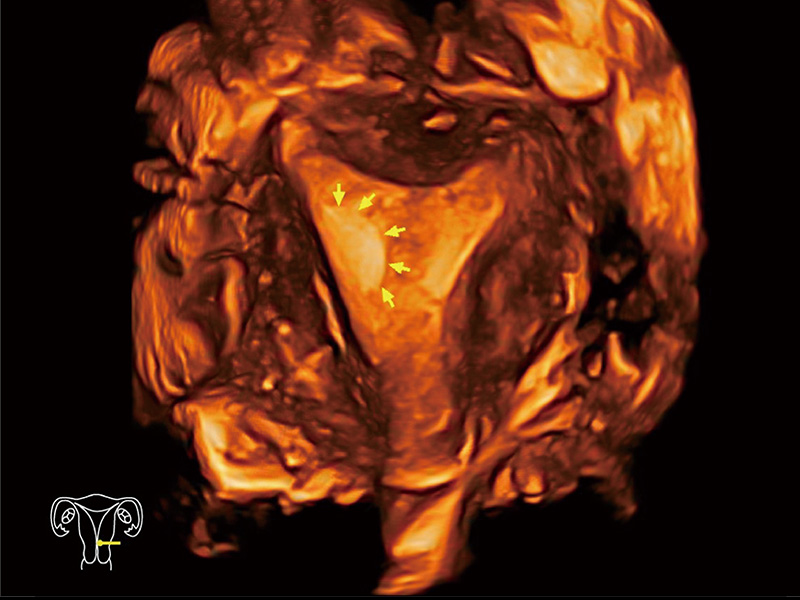

“生育问题”即关系民族复兴,也关系亿万家庭的幸福。随着婚育年龄推迟、社会压力增加等因素,越来越多人群也面临着“生不出、生不好”的问题。辅助生殖作为治疗不孕不育最有效的方法之一,也逐渐成为育儿新希望。而超声检查能为生殖需求人群的初诊评估提供宝贵的信息。 P20 Elite是狗万官方网站匠心打造的一款生殖应用型彩超。她继承狗万官方网站高端极光平台,突破性地将多款新型芯片及硬件模块进行整合,均衡了高端系统性能与小巧灵动机身。P20 Elite卓越的图像质量搭载专科探头,旨在为您提供全面的辅助生殖解决方案。

P20 Elite配备了丰富的生殖探头群和临床应用功能,在卵泡监测、穿刺取卵、胚胎移植、妊娠确认等领域,为生殖需求人群提供了新的临床机会,重新定义高端超声如何应用于生殖健康检查。